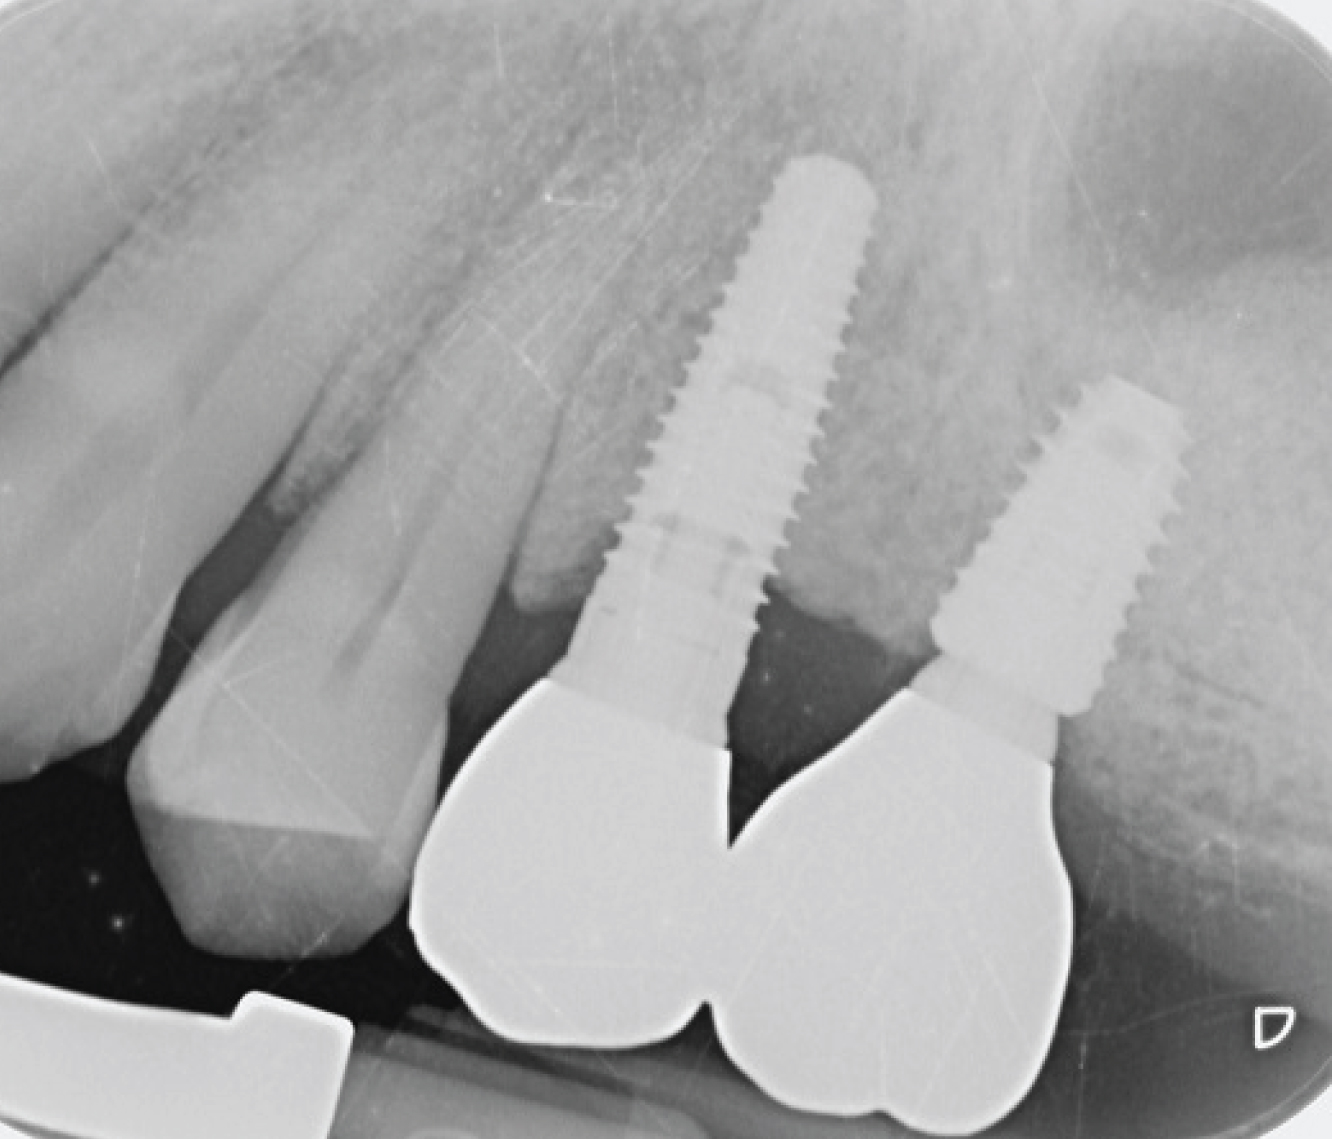

Director’s Clinical Cases

Director’s Clinical Cases